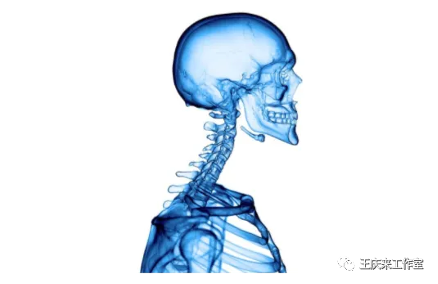

拯救颈椎病的“牵引”

拯救颈椎病的“牵引”拯救颈椎病的“牵引”颈椎病是指颈椎间盘组织退行性改变及其继发病理改变累及周围组织结构,出现颈肩部疼痛、上肢疼痛或麻木感、头痛头晕、恶心呕吐、行走不稳等临床表现,并出现相应的影像学改变。以40岁以上的中老年…查看详情+

躺着治病,“枕”救颈椎

躺着治病,“枕”救颈椎躺着治病, “枕”救颈椎随着社会的发展,工作、生活方式的改变,颈椎病患病人数逐渐增加,并且有年轻化的趋势,但主要的患病人群,仍然以中老年人为主。随着电脑、手机等电子产品的普及,大多数人上班时间需要面对电…查看详情+